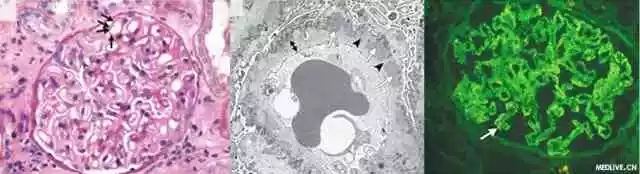

this product is a biochemical reagent and a medical diagnostic drug. it is mainly used as a fluorescent dye in fluorescent antibody technology. it can bind to various antibody proteins. the combined antibody does not lose the specificity of binding to a certain antigen. and has strong green fluorescence in alkaline solution

the maximum emission wavelength is 520~530nm, showing bright yellow-green color. fitc can be stored in a cool, dark and dry place for many years and is currently the most widely used fluorescein. its main advantage is that the human eye is more sensitive to yellow-green, and usually the green fluorescence in sectioned specimens is less than red.